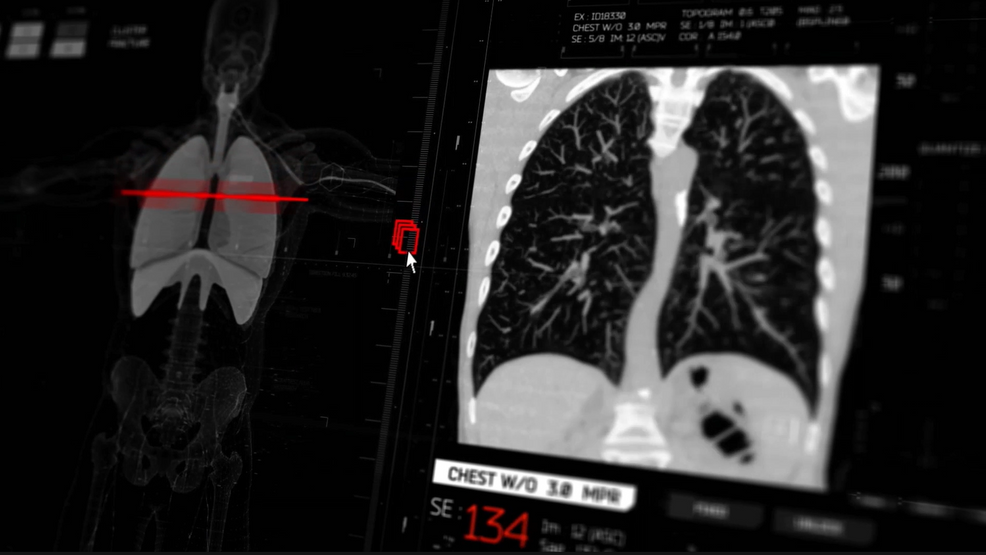

The American Lung Association's "State of Lung Cancer" report highlights that Washington D.C. ranks fourth in the U.S. for lung cancer screening, contributing to a 26% improvement in survival rates over the past five years. Despite these advancements, disparities persist, with Black residents less likely to undergo surgery compared to white residents. The report calls for improved access to advanced diagnostic tools and comprehensive insurance coverage to further enhance early detection and treatment outcomes.